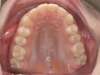

ADULTE

Cas 1 : Description

Après